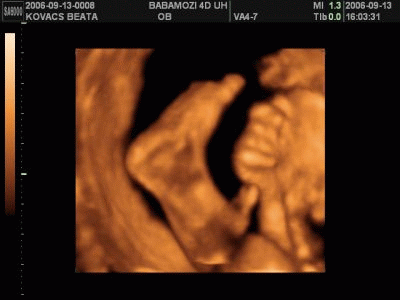

Bea!

Ma mész 4D-re ugye? Várjuk ám a képeket Ádikáról. Azt hallottam, hogy emailen elküldik neked ha kéred.